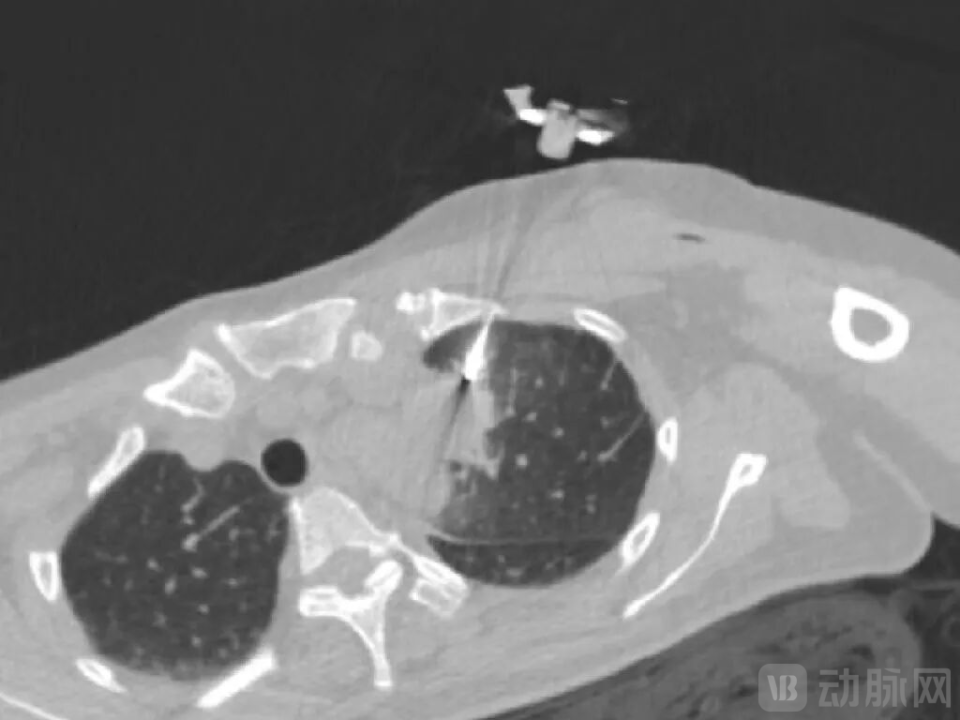

一例患者病例显示,在患者病灶粘连主动脉的情形下,MicrolGT-RoboC执行跨层穿刺规划,自动计算出进针位置及角度,精准穿到病灶。

图片

RoboC规划执行图,图源:微引科技公众号